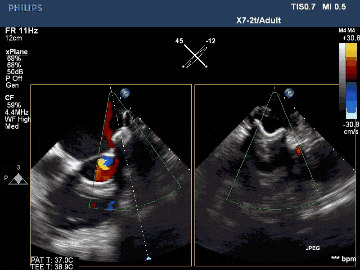

術(shù)后TEE影像示封堵完全

術(shù)后TEE三維重建影像示封堵器位置佳,封堵完全